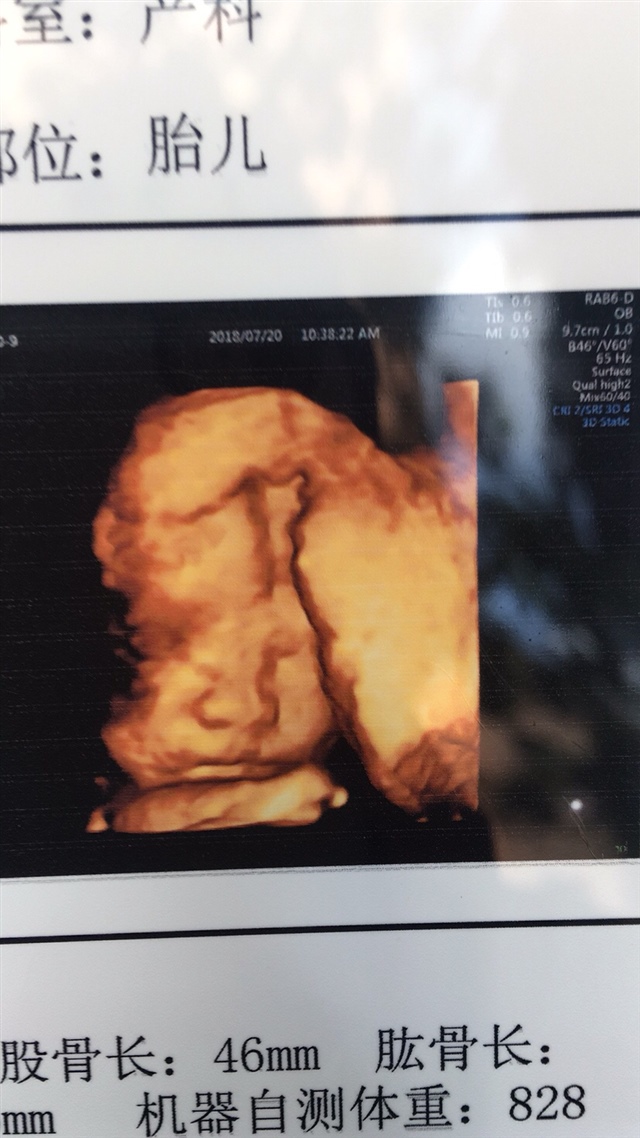

孕29周+4天

应该是女孩